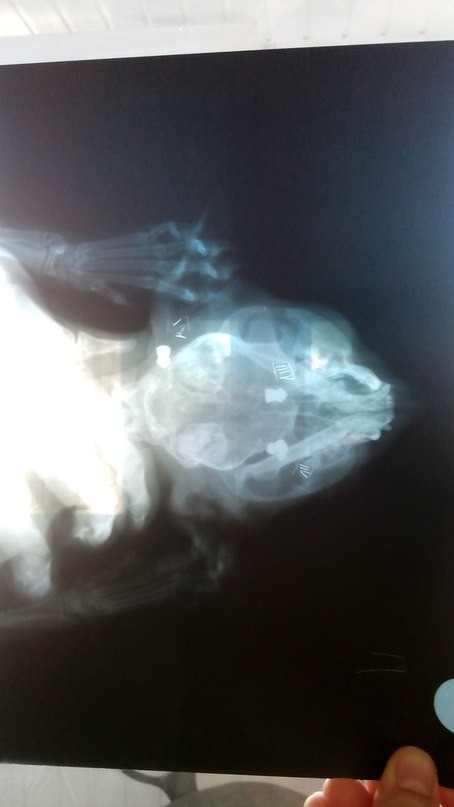

"В теле котёнка было обнаружено 9 пуль. Но, несмотря на боль, кот смог доползти к частному дому за помощью, где его подобрали неравнодушные люди. Сегодня коту будет проведена операция, которая решит его судьбу", — пояснила Екатерина